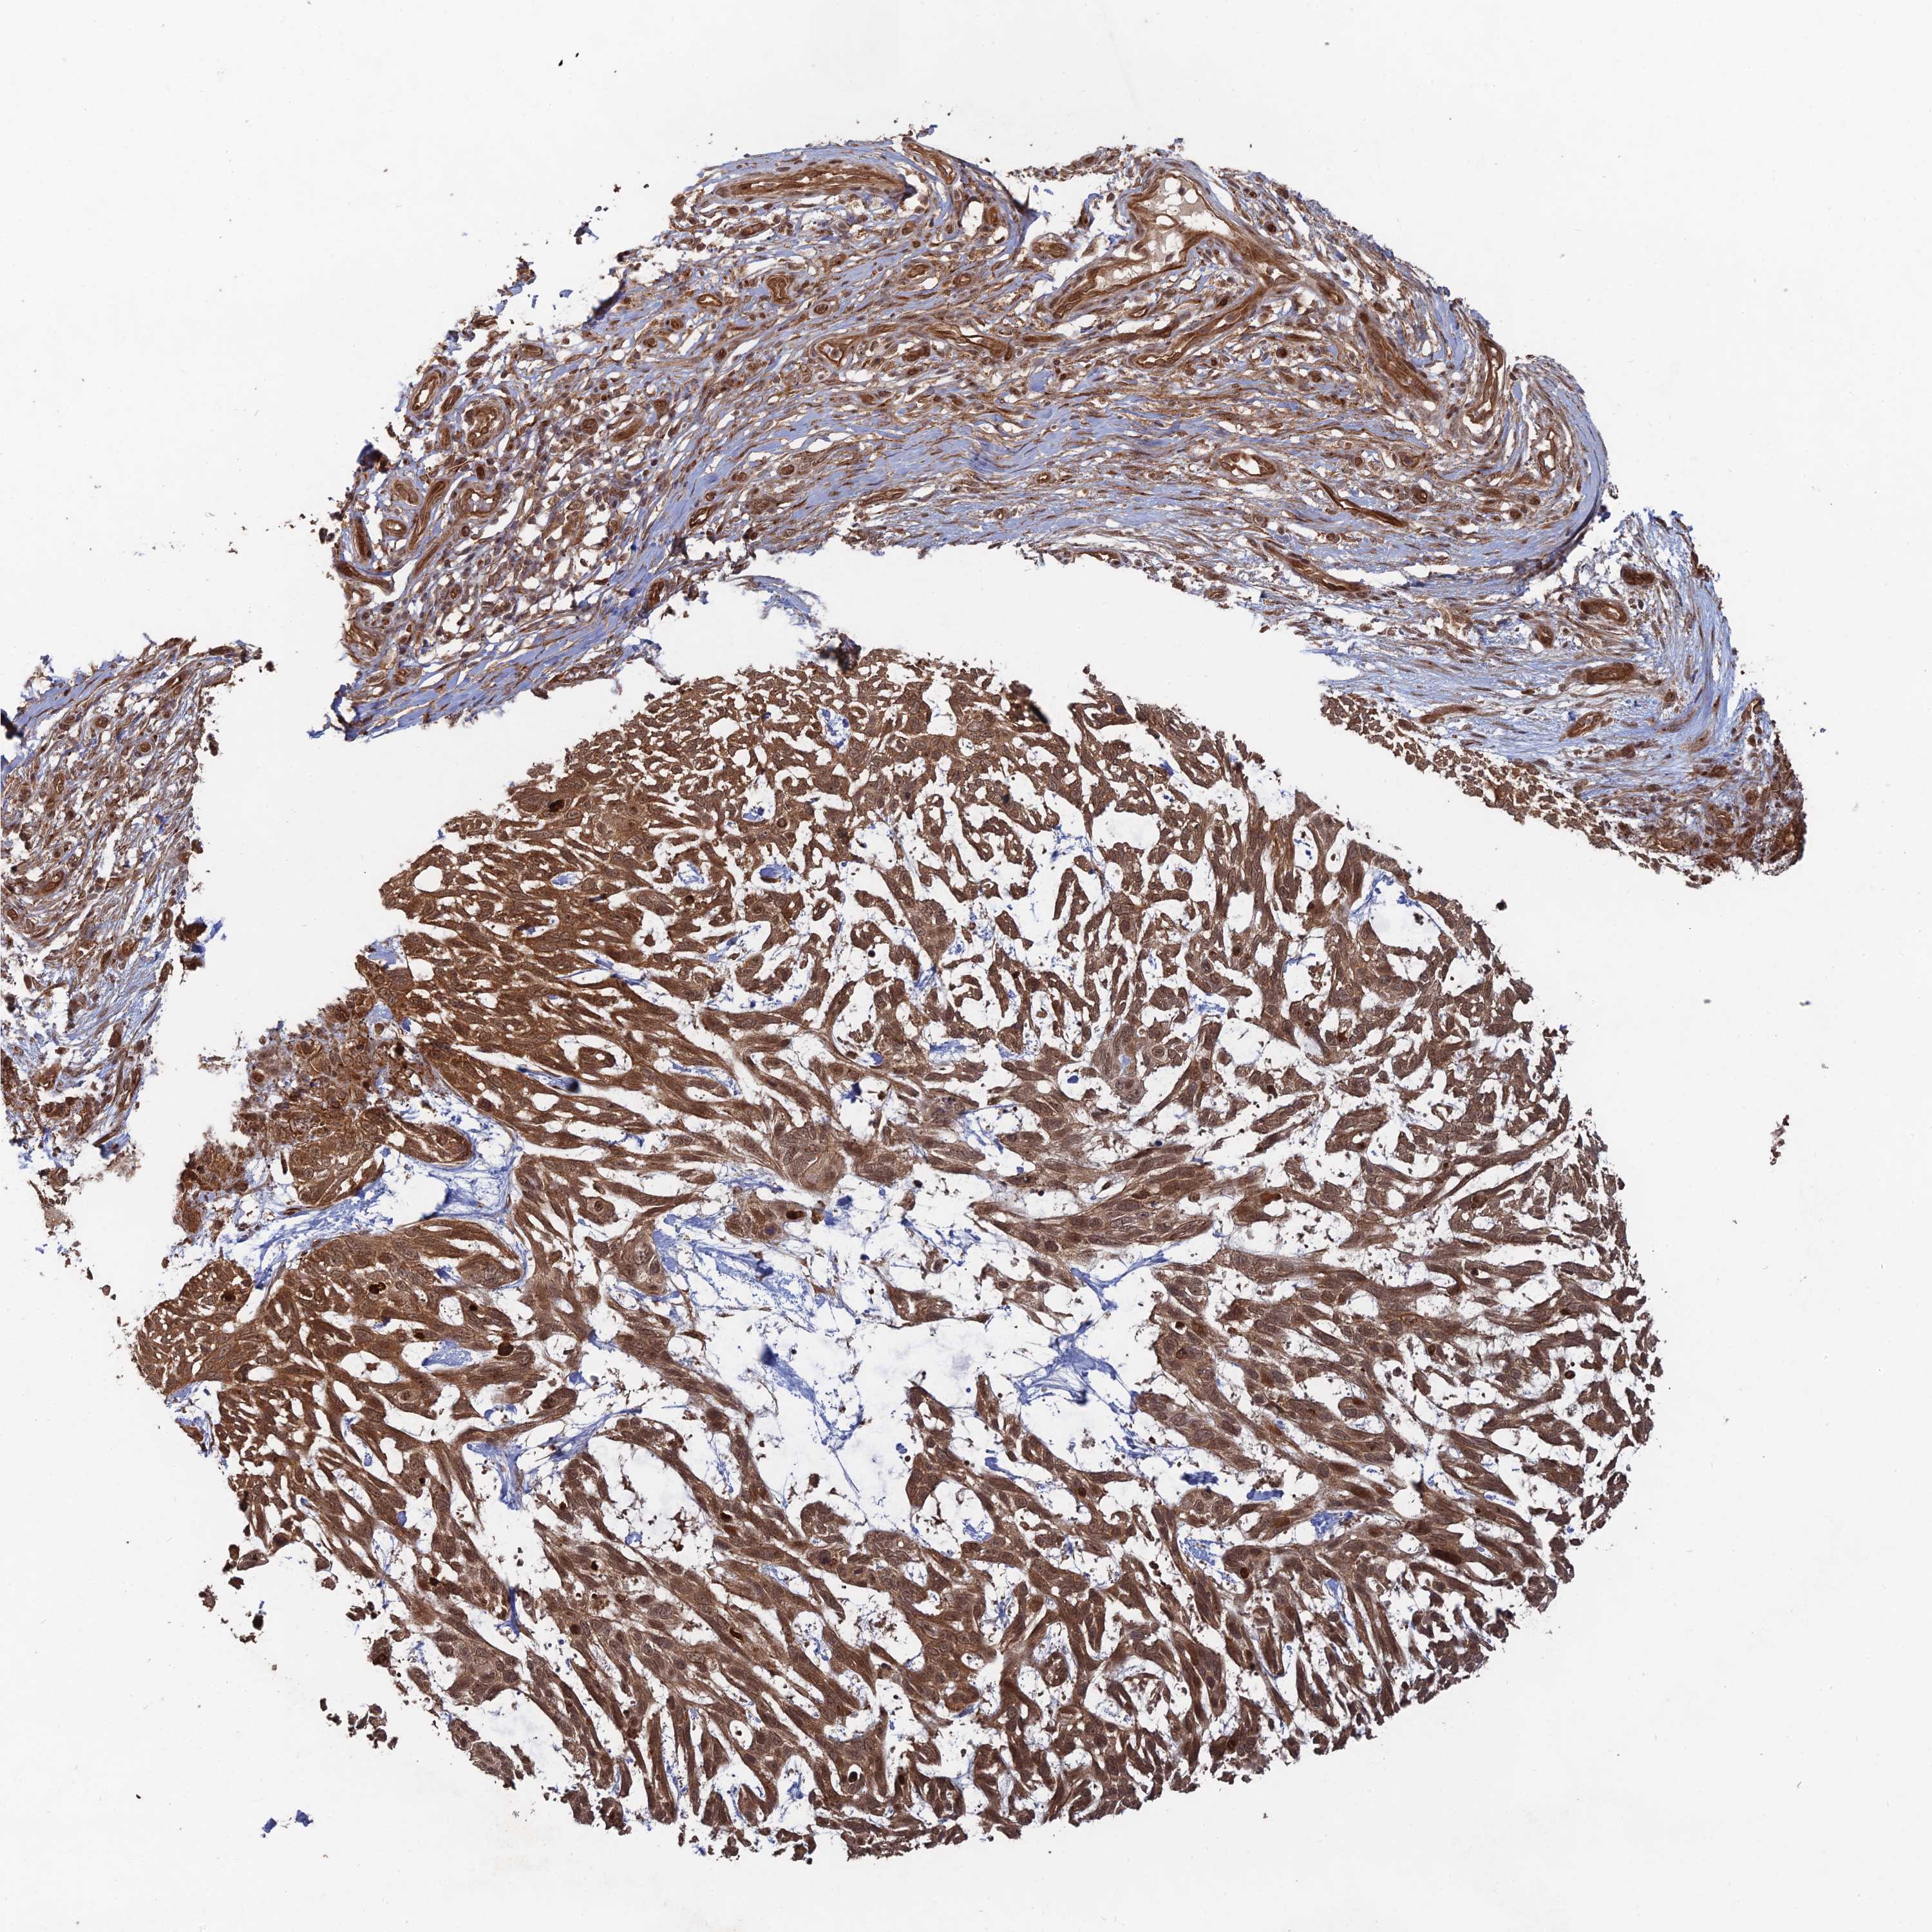

Basal cell and squamous cell cancer

SKIN CANCER - Protein expressioni

A mouse-over function shows sample information and annotation data. Click on an image to view it in a full screen mode. Samples can be filtered based on level of antibody staining by selecting one or several of the following categories: high, medium, low and not detected. The assay and annotation is described here.

Each image is clickable and will lead to virtual microscopy that enables deeper exploration of all samples and also displays staining intensity scores, fraction scores and subcellular localization as well as patient and tissue information for each sample.

Antibody CAB032519

Squamous cell carcinoma, metastatic, NOS